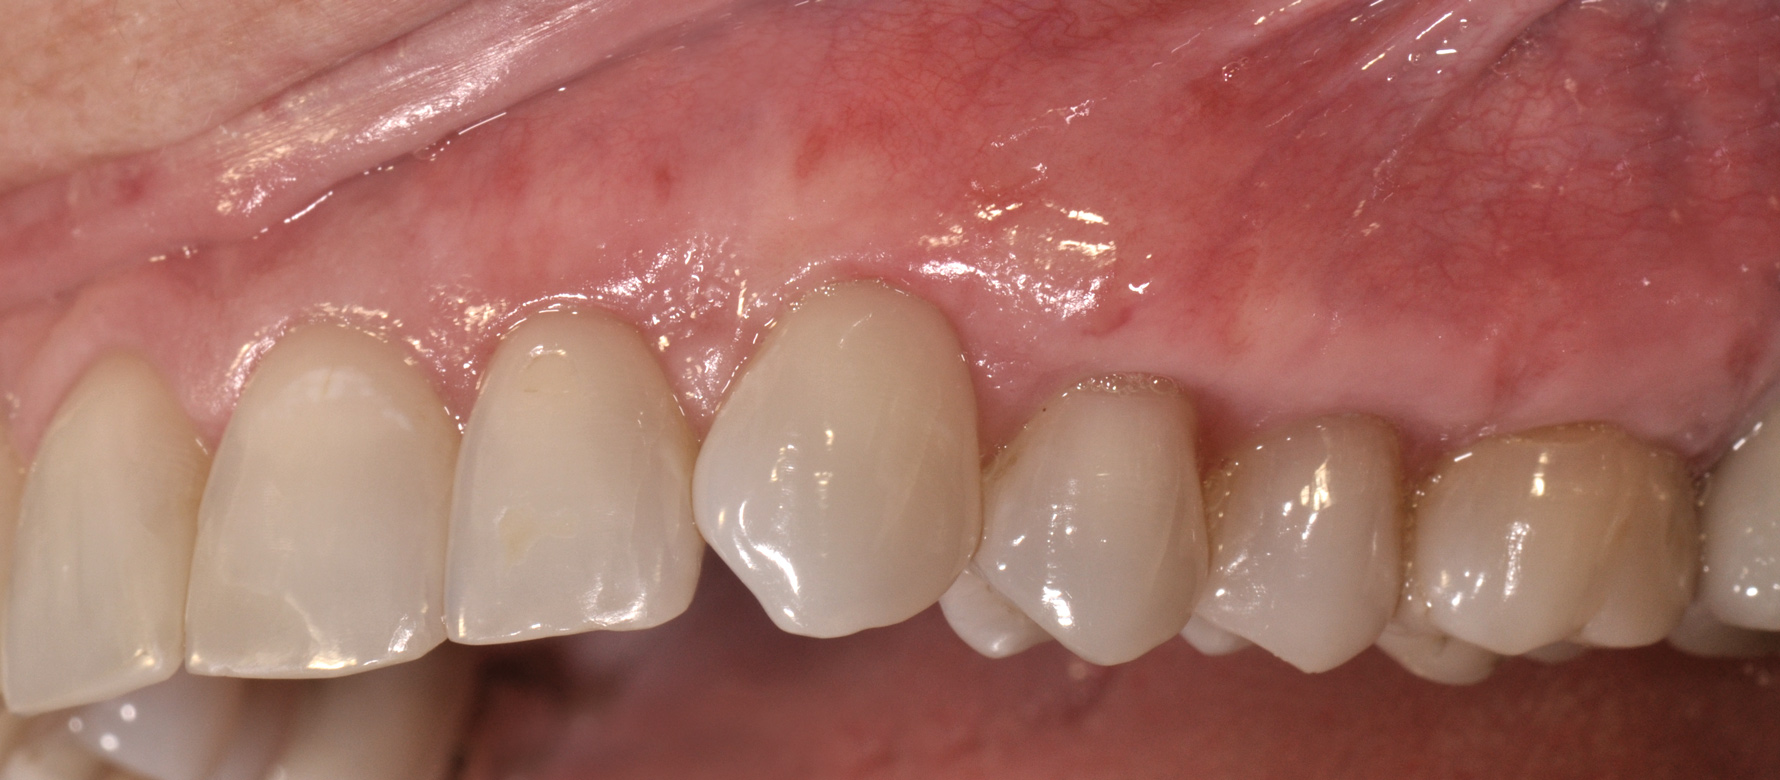

(9.) Gingival recession defect in Quadrant 1.

Figure 9

(10.) Postoperative view of Quadrant 1, 3 weeks after acellular dermal matrix graft.

Figure 10